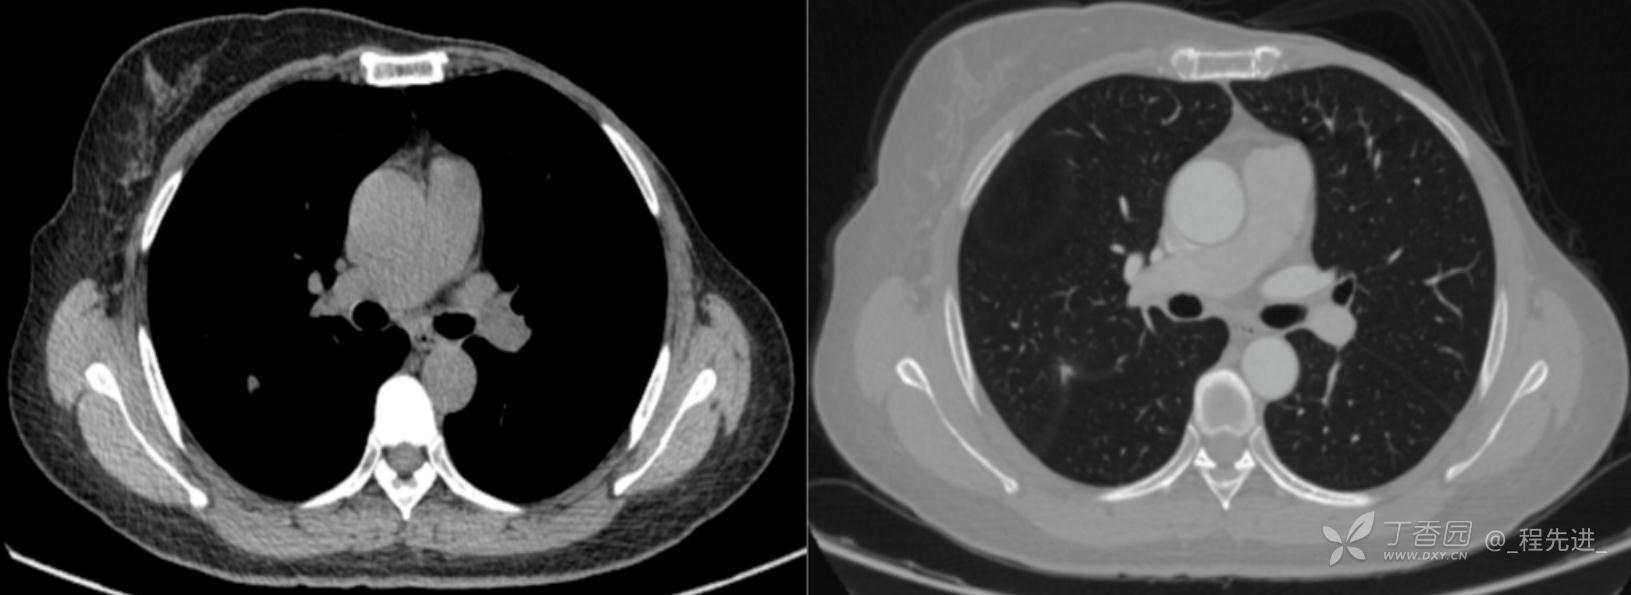

患者性别:女

患者年龄:52岁

简要病史:体检发现右肺上叶结节

既往史:左乳腺癌术后,化疗后